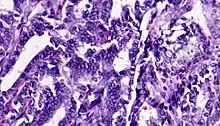

![]() | Adenocarcinoma colon | Micrograph of carcinoma colon showing malignant glands.Nuclei are small and vesicular, located at the bottom of the cell. The cells show increased nucleocytoplasmic ratio. | Category: Histopathology of colorectal adenocarcinoma | Colorectal carcinoma |